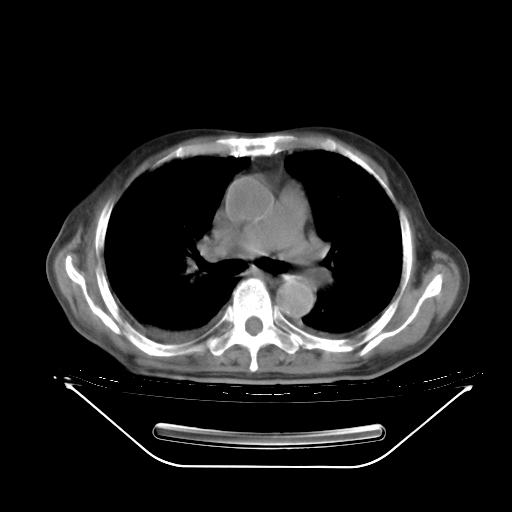

今天复查肺部CT,发现双肺广泛磨玻璃样改变。所以我把3月19日和5月9日相隔50天的肺部CT上传。请大家会诊。

2009年3月19日肺部CT片。

2009年3月19日肺部CT

大致读了系列胸部CT:纵隔窗无明显异常,肺窗:从4、27至今:主要是双肺中下野外带可见毛玻璃样改变,目前处于急性肺泡炎阶段,至于原因考虑1、结替组织或胶原血管性疾病所致?2、恶性疾病如恶组在肺部所致的表现或细支气管肺泡癌?3、药物或其它原因如肺蛋白沉着症所致肺泡炎目前不太可能?总之,明天就去请我院的呼吸科、感染科、血液科和临免专家会诊哈。